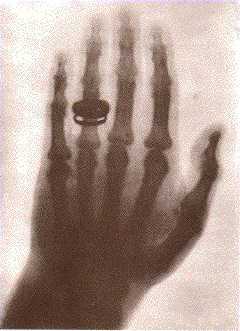

Radiografia da mão de um colega de Wilhelm Carl Röntgen, físico alemão que descobriu os raios X e seu uso para visualização interna da anatomia do corpo humano. Feita em 1895, numa reunião científica em Würtzburg, causou impacto mundial. Artigo